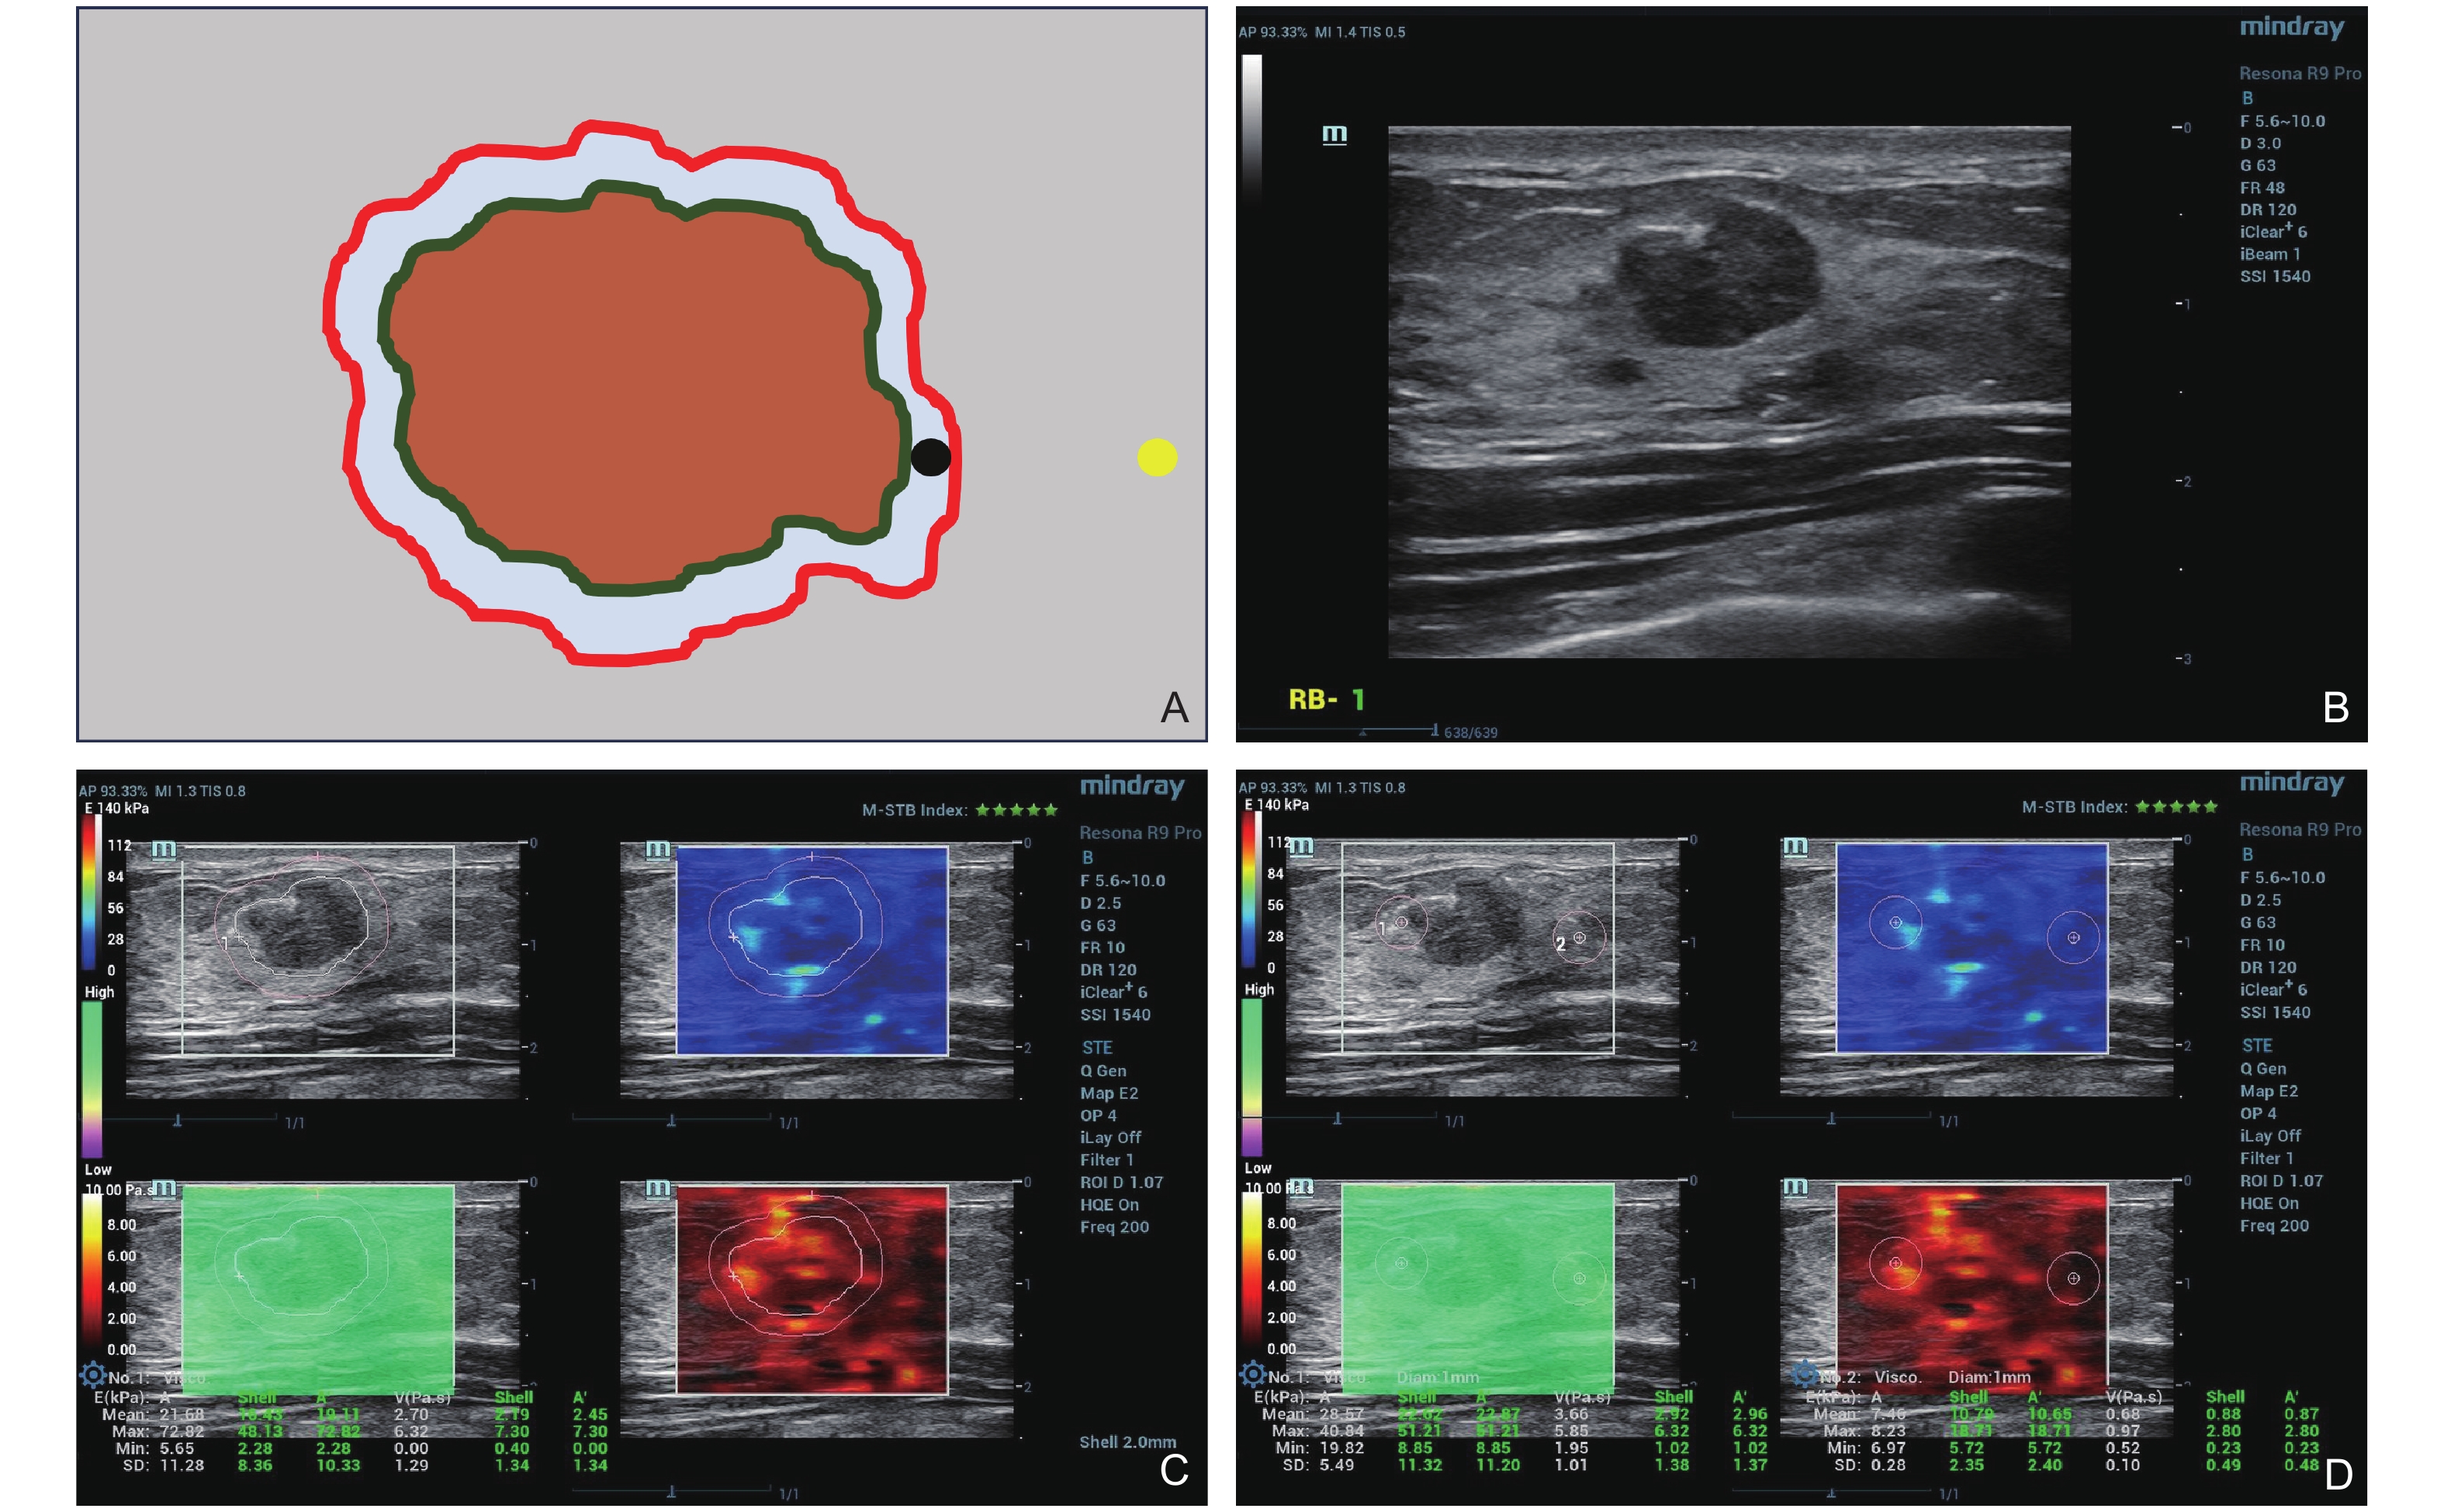

Figure 2

Schematic diagram of ROIs. (A) The gray box is the value box, the orange part is the lesion, the green line is the manually drawn tumor outline, which is ROI-1. The red line is the border automatically drawn by the shell tool. The black circle is ROI-2. The yellow circle is ROI-3. (B-D) Fibroadenoma of a 29-year-old female in the right breast. The red box is the elasticity value, and the blue box is the viscosity value."